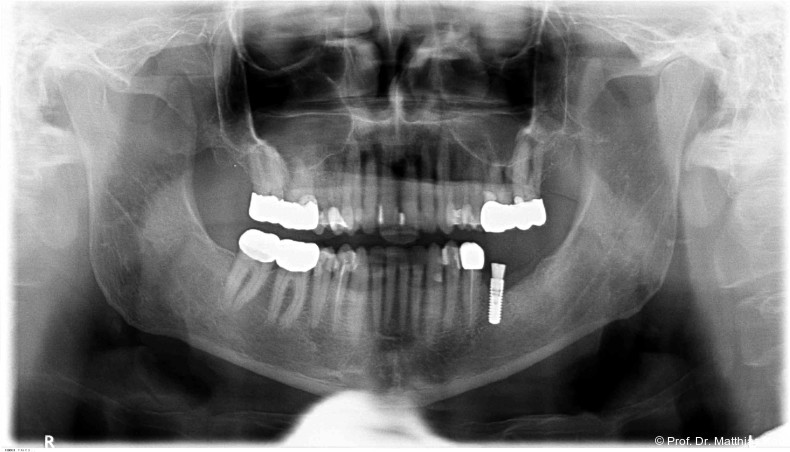

Mikrobewegungen im Verhältnis zum umgebenden Knochenlager. Die Vermeidung solcher Bewegungen ist essenziell, um eine erfolgreiche Osseointegration und damit die Entwicklung einer sekundären, biologisch bedingten Stabilität zu ermöglichen.18 Zur Verkürzung der Behandlungsdauer und zur Ermöglichung einer frühzeitigen prothetischen Versorgung wurden die klassischen operativen Protokolle angepasst. Hierzu zählen die untermaßige Implantatbettpräparation7 sowie der Einsatz konischer Implantatkörper21 (Abb. 1a–2b) mit ausgeprägt aggressiver Gewindegeometrie.8, 14 Beide Maßnahmen führen zu einer erhöhten Kompression des Alveolarknochens, insbesondere in den kortikalen Anteilen.11, 22

Zur Reduktion der Knochenkompression, insbesondere der bukkal gelegenen Lamelle (Abb. 3), werden derzeit Implantate mit dreieckigem Querschnitt10, 12 sowie Implantate mit zervikal reduziertem Durchmesser16 angeboten. Diese scheinen jedoch im Gegensatz zur subkrestalen Positionierung (Abb. 4a–c) von Implantaten23 keine signifikanten Vorteile zu bieten. Bohrprotokolle, welche sowohl auf das jeweilige Implantatsystem als auch auf die vorliegende Knochenqualität abgestimmt sind, haben ebenfalls das Ziel, zu hohe Einbringdrehmomente zu vermeiden.